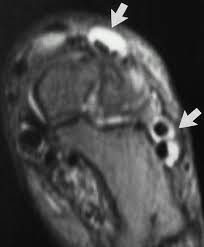

Pitfalls In Mri Of The Developing Pediatric Ankle Radiographics

Pitfalls In Mri Of The Developing Pediatric Ankle Radiographics from pubs.rsna.org